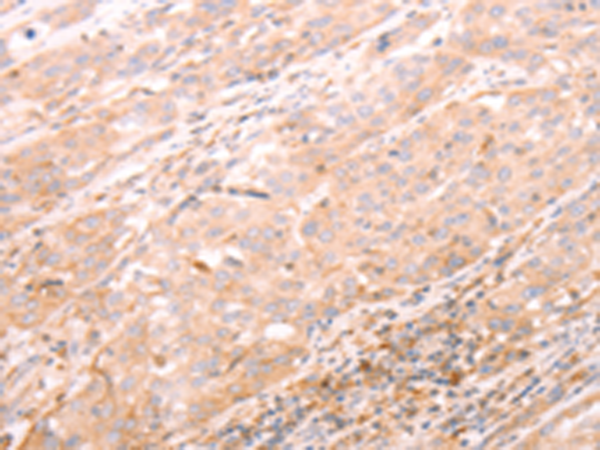

分类: 科研抗体货号: P04280别名: AT2; ATGR2; MRX88应用: IHC反应种属: Human, Mouse, Rat